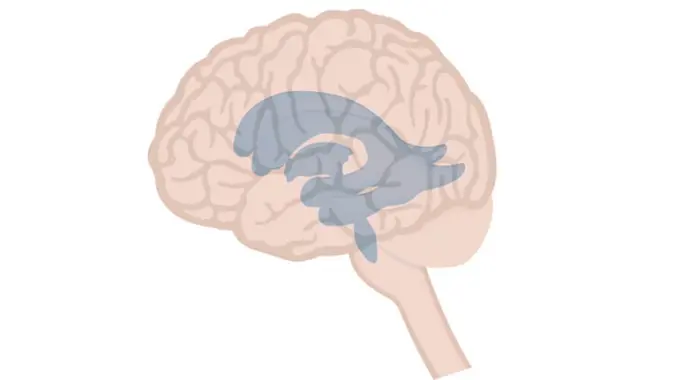

تُشكل بطينات الدماغ شبكة من التجاويف المترابطة التي تقع في أعماق الدماغ. هذه الهياكل الأربعة ليست مجرد فراغات، بل هي جزء حيوي من الجهاز العصبي المركزي، وتحتوي على سائل مهم لدعم الدماغ وحمايته.

يتكون نظام بطينات الدماغ من أربع تجاويف رئيسية تتصل ببعضها البعض: بطينان جانبيان، وبطين ثالث، وبطين رابع. كل منها له موقعه ودوره الخاص.

- البطينان الجانبيان: هما الأكبر ويقعان في نصفي الكرة المخية.

- البطين الثالث: يوجد في خط الوسط للدماغ، أسفل البطينين الجانبيين.

- البطين الرابع: يقع بين جذع الدماغ والمخيخ.

تتصل هذه البطينات عبر ممرات دقيقة، مثل الثقبة بين البطينين الجانبيين والثالث، والقناة الدماغية بين البطينين الثالث والرابع. هذا الترابط يضمن تدفق السائل بسلاسة.